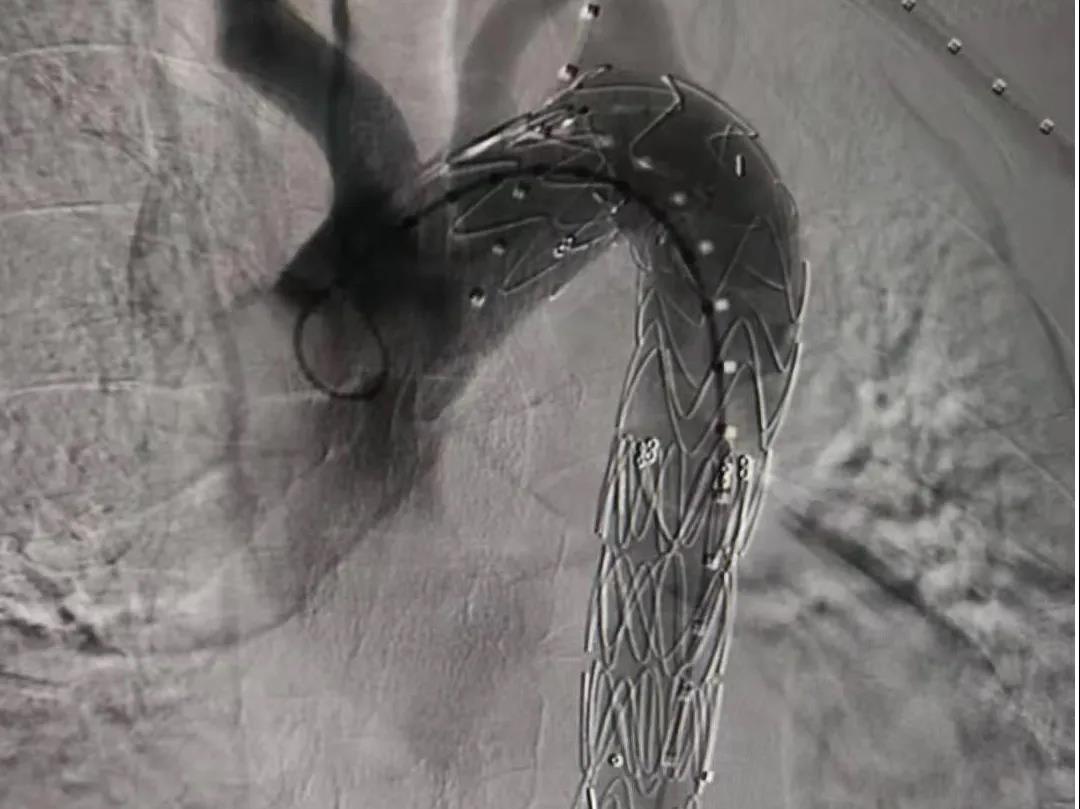

12月26日,我院胸外科介入团队在甘肃省人民医院心血管专家的指导下,成功为一位主动脉夹层患者实施了微创介入治疗,挽救了一条鲜活的生命,此项技术的开展填补了我市主动脉夹层治疗领域的空白。

患者入院后,胸外科主任尹义学高度重视,随即邀请麻醉科、ICU、介入科同事进行病情讨论,最终决定行主动脉腔内隔绝术治疗。经过科室严谨的术前准备后,于甘肃省优势学科医联体平台,邀请甘肃省人民医院心血管外科尤涛教授及团队前来会诊指导手术,手术历时2小时顺利完成,取得圆满成功。

主动脉夹层是主动脉疾病里最凶险的一个疾病,起病非常急,血管外膜一旦破裂,患者大出血就会死亡。我市由于交通不便,许多主动脉夹层患者在转院途中不幸身亡,为了能够尽可能挽救这一部分患者的生命,我院领导与西京医院心血管外科建立合作平台,先后派出我院医务人员进行学习,引进技术,并积极参与甘肃省优势学科联盟建设,让患者能够在家门口得到有效救治,减轻了患者外出求医的种种不便,而且进一步提升了我院的专业技术水平与服务能力。